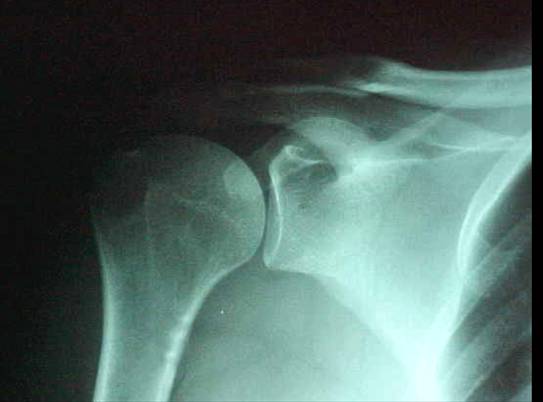

RX No. 1: AP Corrigido em rotação Neutra